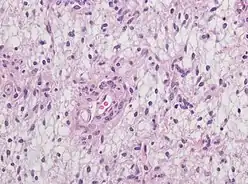

Neuropathology

Neuropathology is a specialty within the study of pathology focused on the disease of the brain, spinal cord, and neural tissue.[33] This includes the central nervous system and the peripheral nervous system. Tissue analysis comes from either surgical biopsies or post mortem autopsies. Common tissue samples include muscle fibers and nervous tissue. Common applications of neuropathology include studying samples of tissue in patients who have Parkinson's disease, Alzheimer's disease, dementia, Huntington's disease, amyotrophic lateral sclerosis, mitochondria disease, and any disorder that has neural deterioration in the brain or spinal cord.[34][35]

History

While pathology has been studied for millennia only within the last few hundred years has medicine focused on a tissue- and organ-based approach to tissue disease. In 1810, Thomas Hodgkin started to look at the damaged tissue for the cause. This was conjoined with the emergence of microscopy and started the current understanding of how the tissue of the human body is studied.[36]